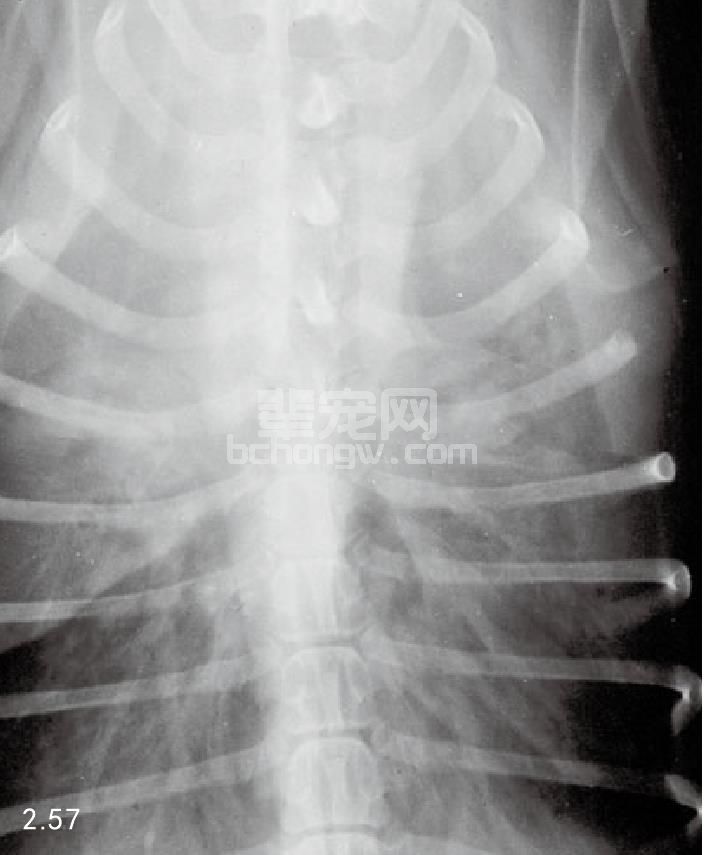

图2.57 患有扩散型前部胸腔纵隔加宽的金毛猎犬的背腹侧胸腔X线片。